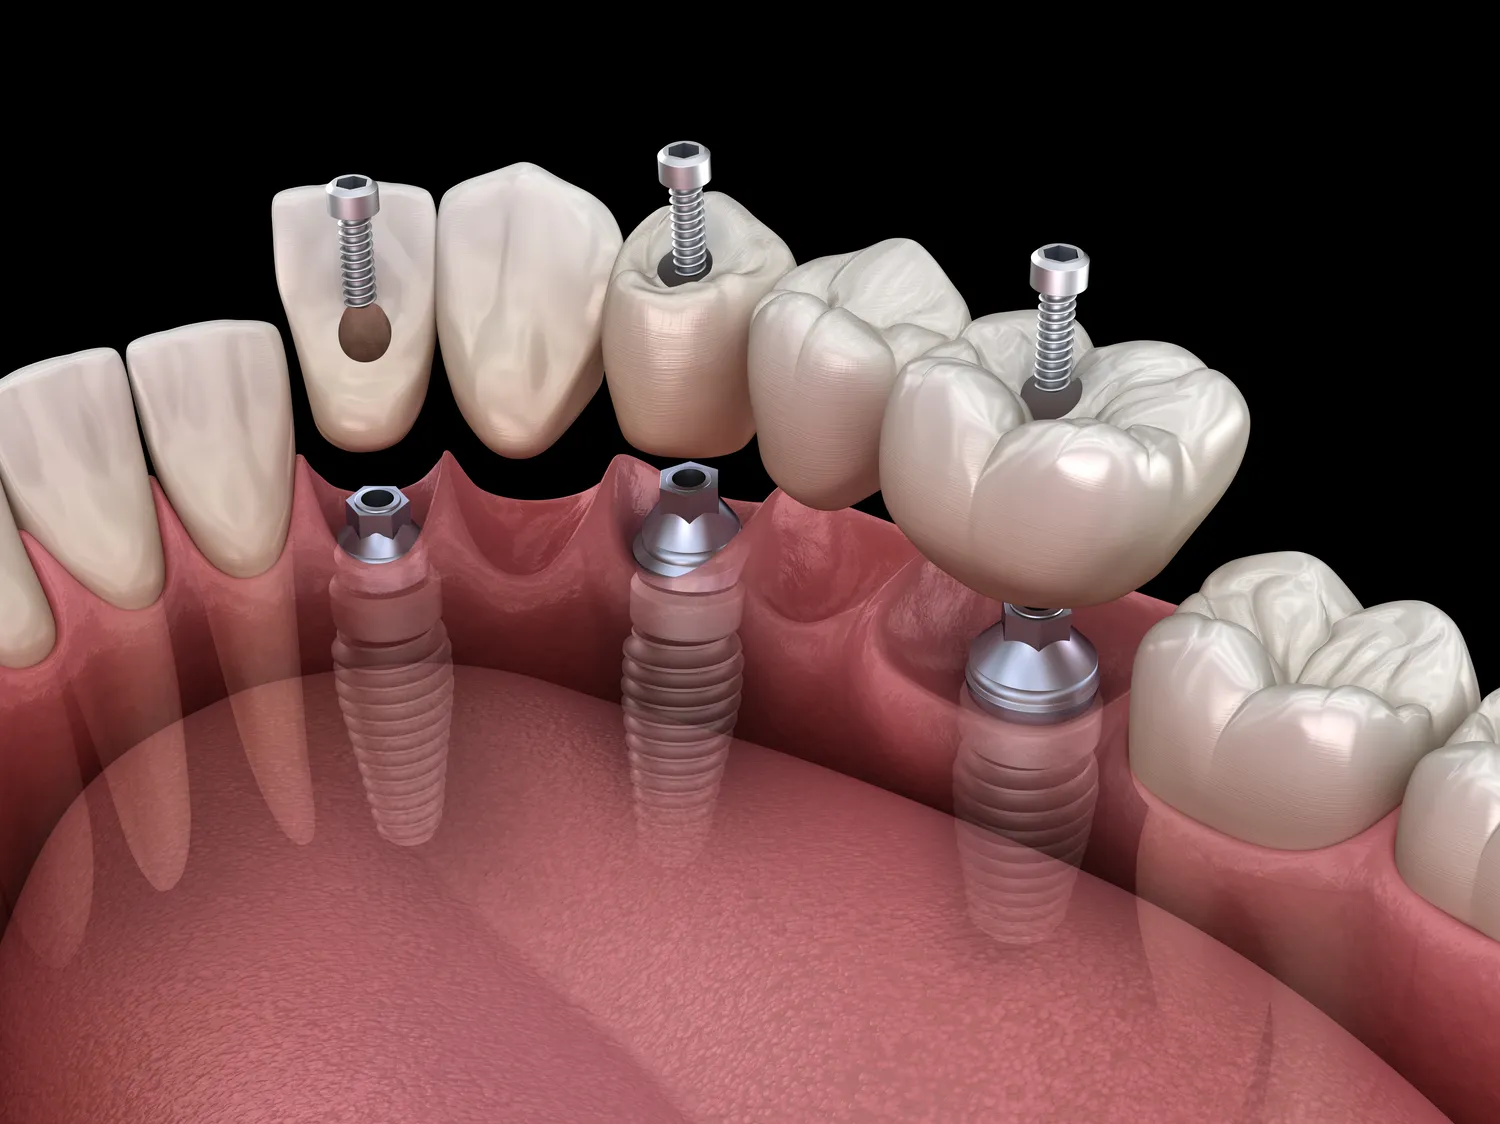

Procedura wszczepienia implantu stomatologicznego w Szczecinie, podobnie jak w innych miejscach, jest procesem wieloetapowym, wymagającym precyzji i doświadczenia lekarza. Pierwszym krokiem, po dokładnej diagnostyce i zaplanowaniu leczenia, jest etap chirurgiczny. W zależności od indywidualnej sytuacji pacjenta, może on obejmować przygotowanie miejsca pod implant, często poprzez wykonanie niewielkiego nacięcia w dziąśle, aby uzyskać dostęp do kości. Następnie, przy użyciu specjalnych wierteł, lekarz precyzyjnie przygotowuje łożysko w kości, idealnie dopasowane do rozmiaru wybranego implantu.

Kolejnym etapem jest umieszczenie implantu w przygotowanym łożysku. Jest to zazwyczaj procedura bezbolesna, wykonywana w znieczuleniu miejscowym, dzięki czemu pacjent nie odczuwa dyskomfortu. Po wszczepieniu implantu, dziąsło jest zamykane szwami. Następuje okres gojenia, który trwa zazwyczaj od kilku tygodni do kilku miesięcy. W tym czasie kość szczęki lub żuchwy integruje się z powierzchnią implantu, tworząc stabilne i trwałe połączenie – proces ten nazywa się osteointegracją. W niektórych przypadkach, zwłaszcza gdy pacjentowi zależy na jak najszybszym odtworzeniu estetyki, możliwe jest tymczasowe obciążenie implantu specjalną koroną tymczasową.

Po zakończeniu procesu osteointegracji następuje etap protetyczny. Lekarz odsłania implant, jeśli był on przykryty dziąsłem, i przykręca do niego śrubę gojącą, która kształtuje dziąsło wokół przyszłego zęba. Po kilku dniach śruba gojąca jest usuwana, a na jej miejsce przykręcana jest śruba protetyczna lub łącznik, do którego następnie mocowana jest docelowa korona protetyczna. Korona jest wykonywana indywidualnie w laboratorium protetycznym, na podstawie wycisków pobranych od pacjenta, tak aby idealnie pasowała kolorem, kształtem i rozmiarem do pozostałych zębów. Po osadzeniu korony leczenie implantologiczne jest zakończone, a pacjent może cieszyć się nowym, pełnym uśmiechem. Regularne kontrole i odpowiednia higiena jamy ustnej są kluczowe dla utrzymania długoterminowego sukcesu implantacji.